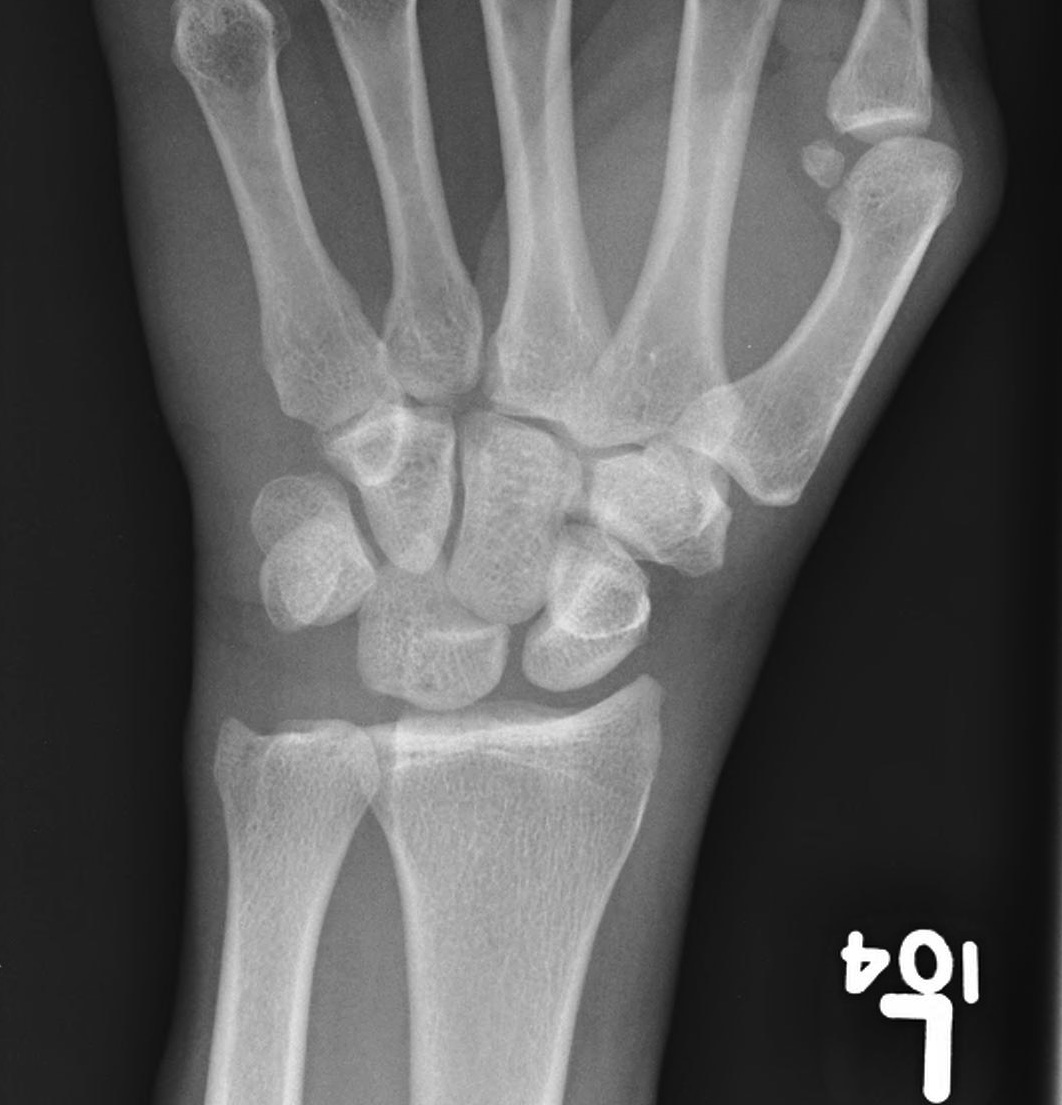

X-ray

Disruption of Gilula's 3 smooth carpal arcs

Progressive Injury

1. Capitate dorsal

- lunate remains with radius

- lunate looks triangular on AP

2. Lunate dislocates

- usually volar

2 main groups of injury

1. Dorsal trans-scaphoid dislocation

- 2/3 of cases

2. Dorsal perilunate dislocation

- 1/3 of cases